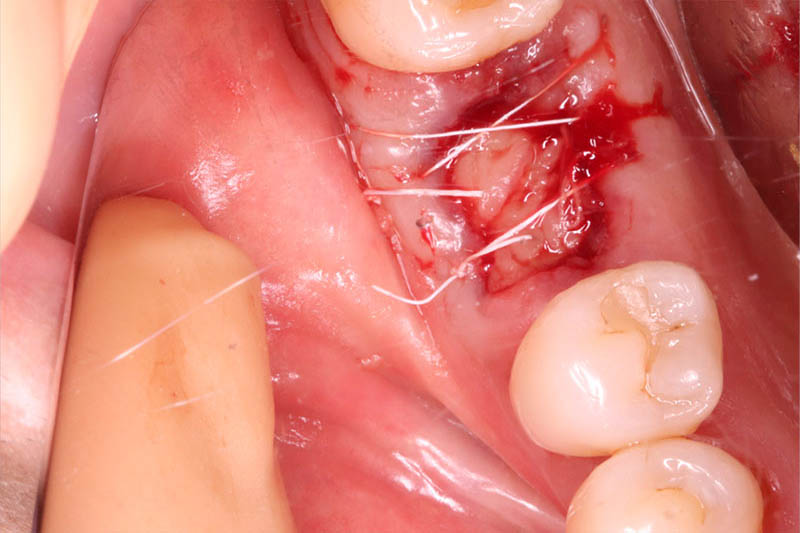

またインプラント症例①でも行ったように抜歯窩の保存をするために、抜歯時にPRGFを抜歯窩に充填しました。

インプラント埋入手術

インプラントの埋入に関しては1回法で行いました。抜歯した部位の骨はしっかりと治癒していました。インプラント埋入後はヒーリングキャップを装着しました。手術時は特に大きな問題はなく無事に手術が終了しました。インプラントの露出を避けるためにも骨幅が少しでも広いところに埋入するために理想的な位置よりは少し後ろになっています。